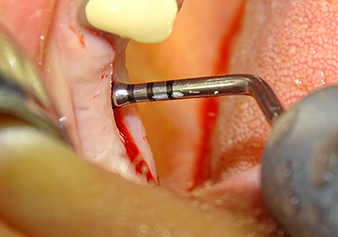

Following an intermediate check (Fig. 4) a further preparation step was performed (Fig. 5). Afterwards, the hydraulic Z35P instrument was used to lift the membrane to the desired position (Fig. 6 and 7). This was followed by further piezosurgical preparation of the implant bed, concluded with a rotary bur and shoulder milling cutter up to the implant diameter of 4.8 mm. Before the implant was inserted, the augmentation material (particle size approx. 0.8-1.6 mm) was introduced underneath the Schneiderian membrane (Fig. 8).